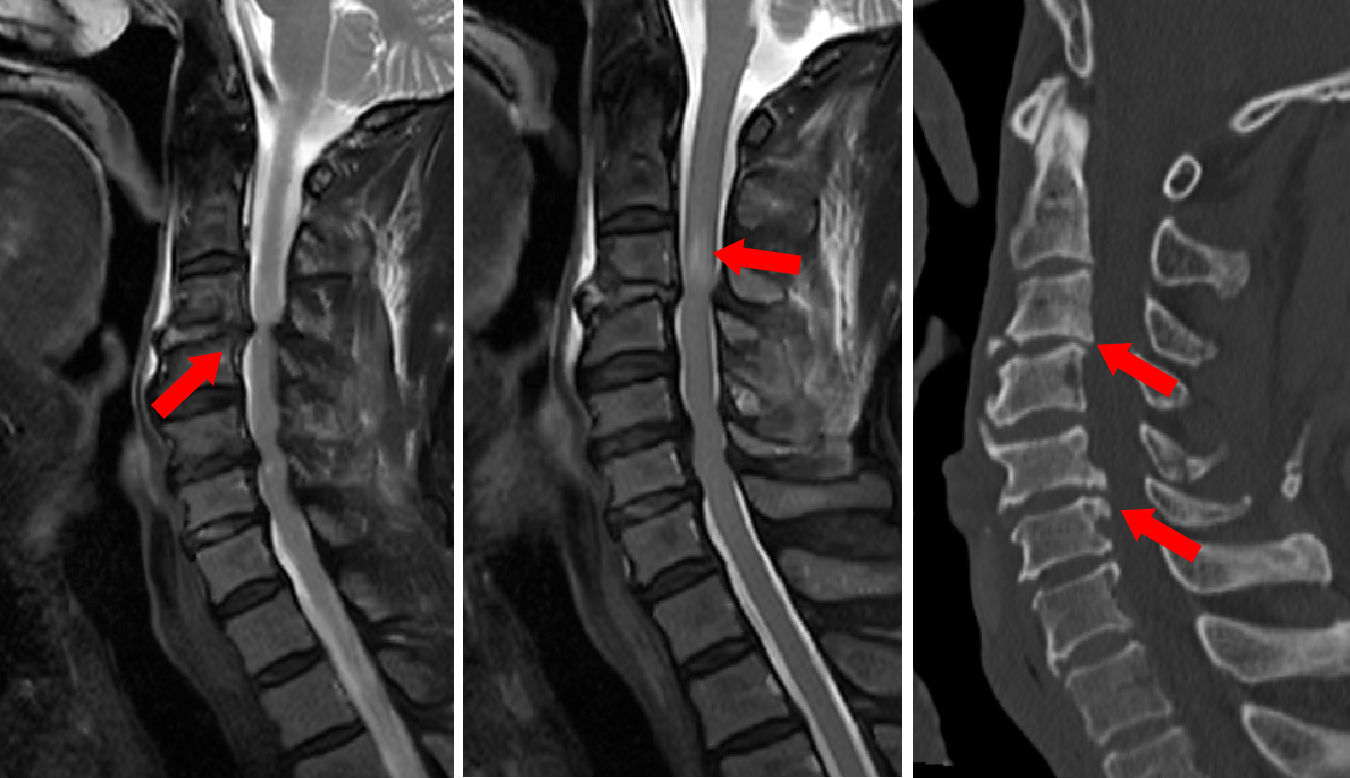

图2 MRI和CT见脊髓受压水肿及骨刺等

“患者脊髓型颈椎病外伤后瘫痪合并脑出血,全员准备”。120急救人员的声音打破抢救室的嘈杂,分诊护士栗宏刚和护士长陈慧玲几乎在同时赶赴患者身旁,抢救室瞬间进入战斗状态。创伤中心主治医师张骞、孟哲快速评估患者生命体征并开启急救措施,神经外科张培海医生紧急赶赴创伤中心查看患者,评估患者损伤程度及脊髓损伤平面。面对患者复杂病情,张培海医生团队第一时间联系放射科申请紧急颈椎核磁共振(MRI)检查,明确脊髓受压节段及损伤程度。同时,联合创伤中心、重症医学科、麻醉科、心脏外科专家会诊,全面评估患者心脏功能、凝血状态及手术耐受性,最终敲定“急诊颈椎椎管减压+颈椎植骨融合内固定术”的具体方案。